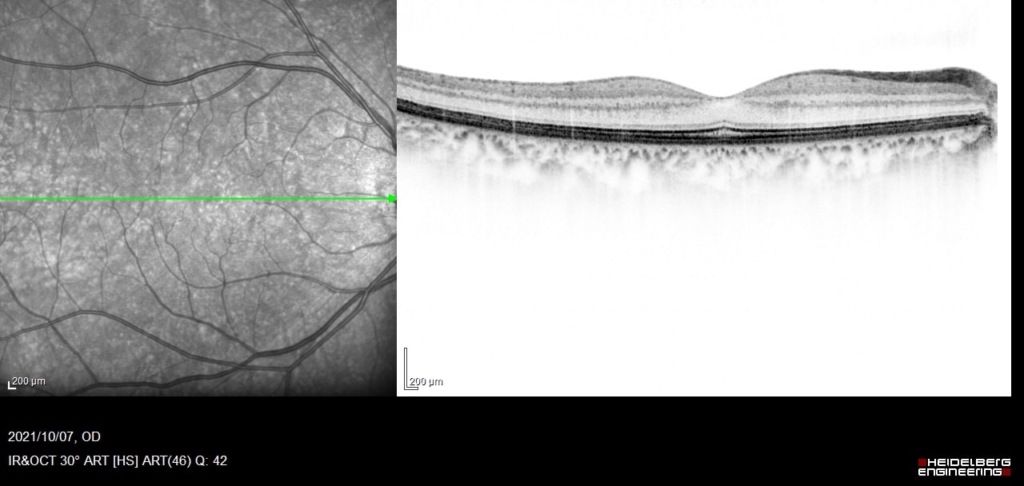

60歳 女性

主訴 10日前から飛蚊症、2日前から視野欠損を自覚

視力 右眼 0.6(1.2×-0.75)

鼻上側に剥離が剥離があり、格子状変性の耳側縁に馬蹄形裂孔がみられる。